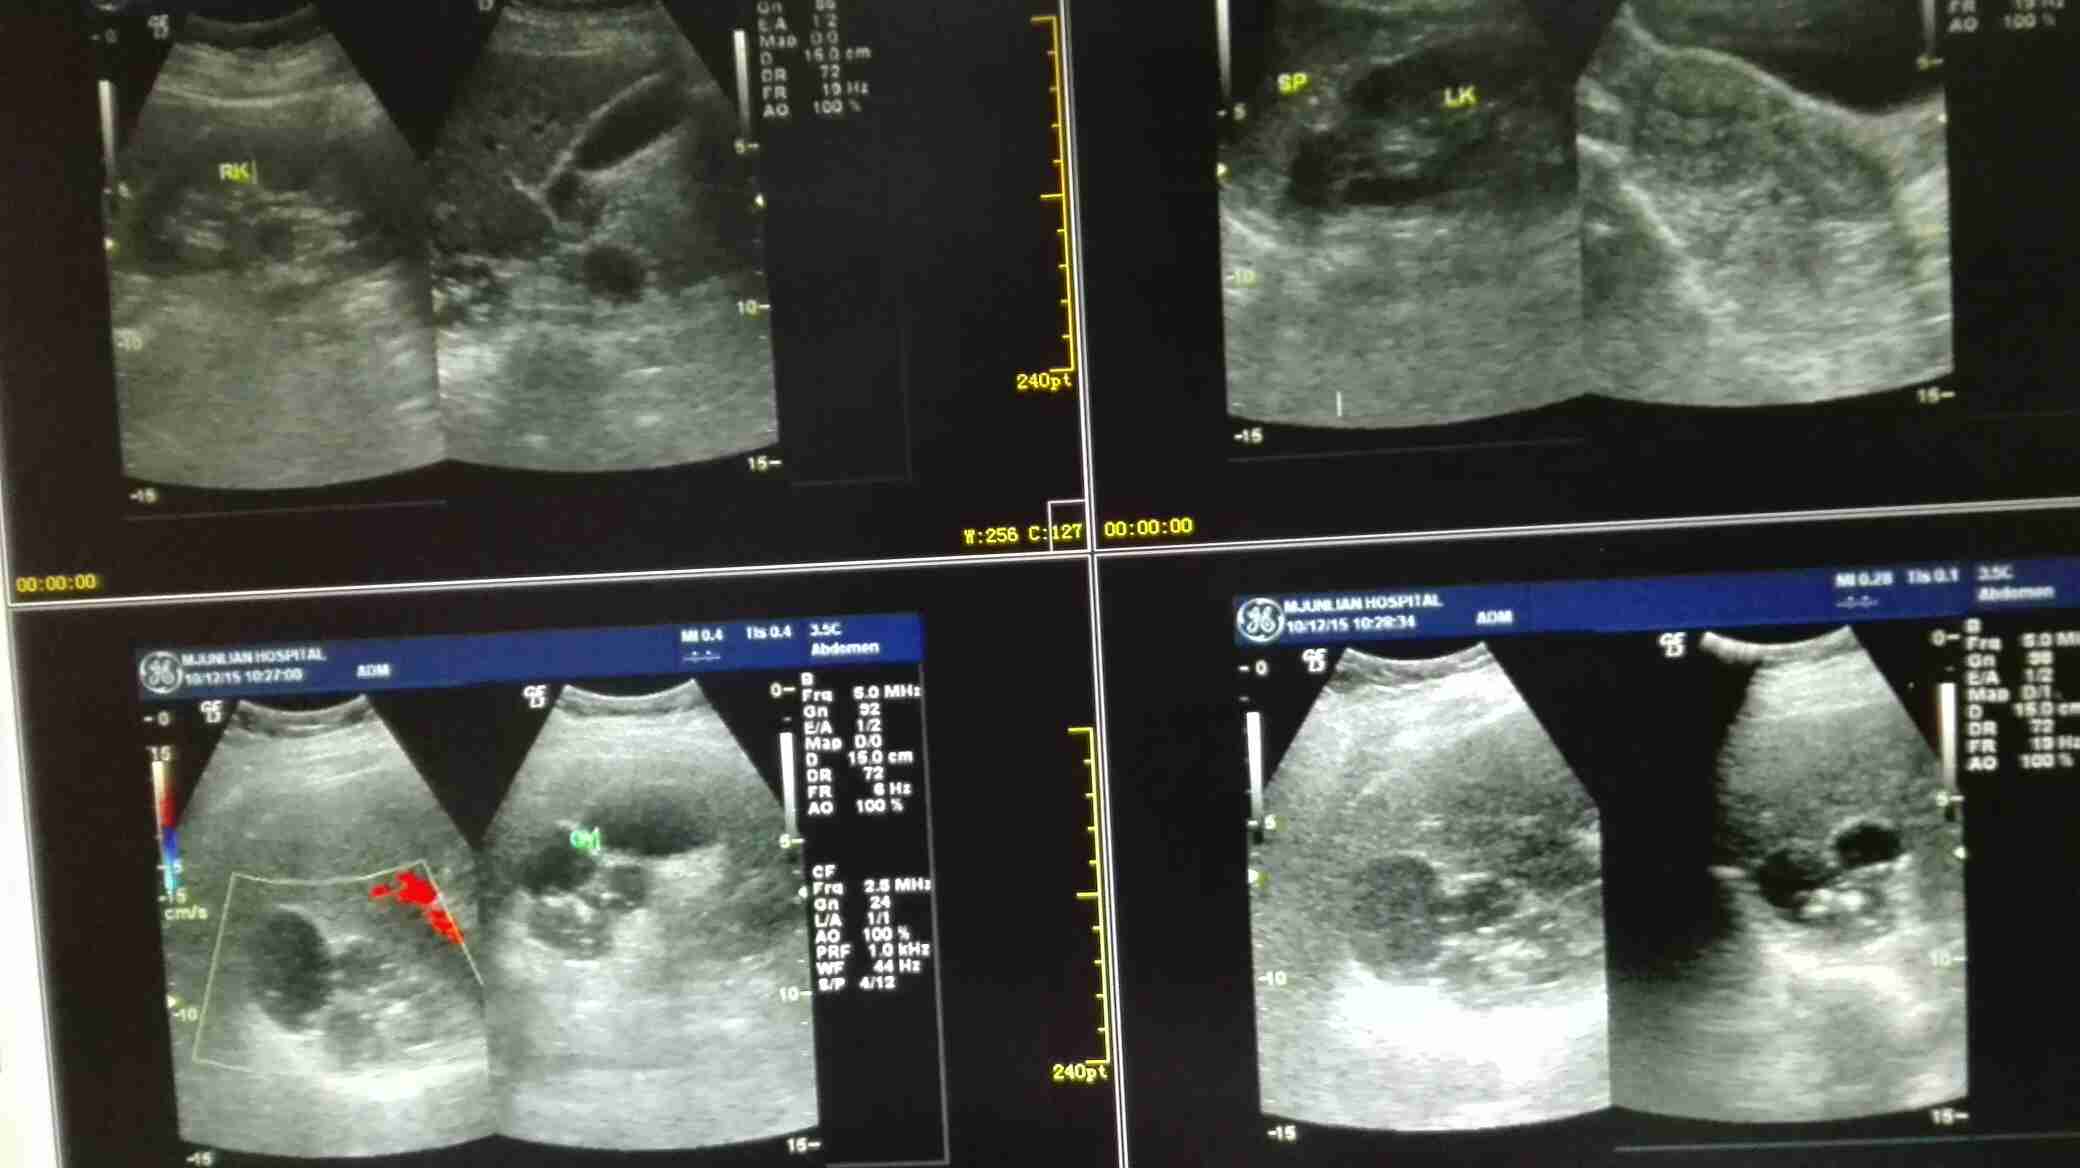

患者女,40岁,医院职工家属。B超体检时发现肝肾间多发囊性占位性病变。行腹部平扫示:右肾上腺区囊性占位,有分割和钙化点,右肾受压下移。诊断意见:右肾上腺囊腺瘤可能性大,建议进一步检查明确。后到市级医院检查并切除手术,病理切片考虑肾上腺囊肿。今腰部不适复查CT片。